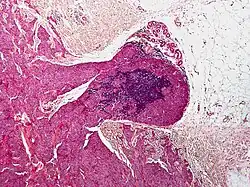

Histopathology